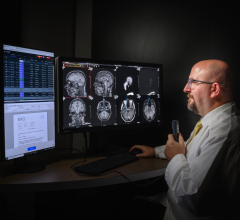

November 2, 2012 — ClearCanvas Inc. announced the commercial release of ClearCanvas radiology information systems/picture archive and communications systems (RIS/PACS) Team Edition, an end-to-end radiology workflow management solution.

The system is U.S Food and Drug Administration (FDA) cleared and CE marked and provides fully integrated radiology workflow and data management solution.

The RIS/PACS is built on the popular ClearCanvas software platform, currently in use by over 25,000 users and partners. The easy to use workflow solution has been designed to enable a practice to efficiently serve patients from the time they walk in the door to the time they receive their results.

The Team Edition includes key features such as drag and drop scheduling, customizable work lists, roaming user profiles, hanging protocols and digital report dictation. With web-based image viewing and the Referring Physician's Portal, it has also been designed for efficient and easy access to both patient images and associated reports.